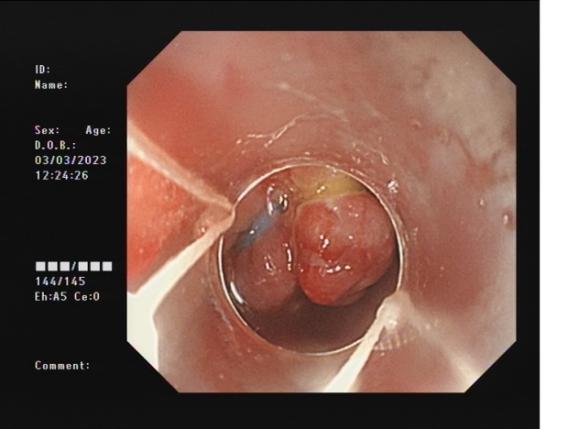

直腸側向發育性腫瘤 內鏡下黏膜下剝離術后創面

內鏡下黏膜剝離術(ESD):治療巨大平坦息肉,早期癌及癌前病變,黏膜下腫瘤等。